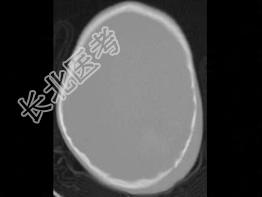

- 单项选择题男,3岁, 头颅被球击中,请结合CT图像, 选择最可能的诊断是  (    )

A、高血压性脑出血

B、脑结核

C、脑挫裂伤血肿形成

D、动脉瘤破裂出血

E、血管畸形